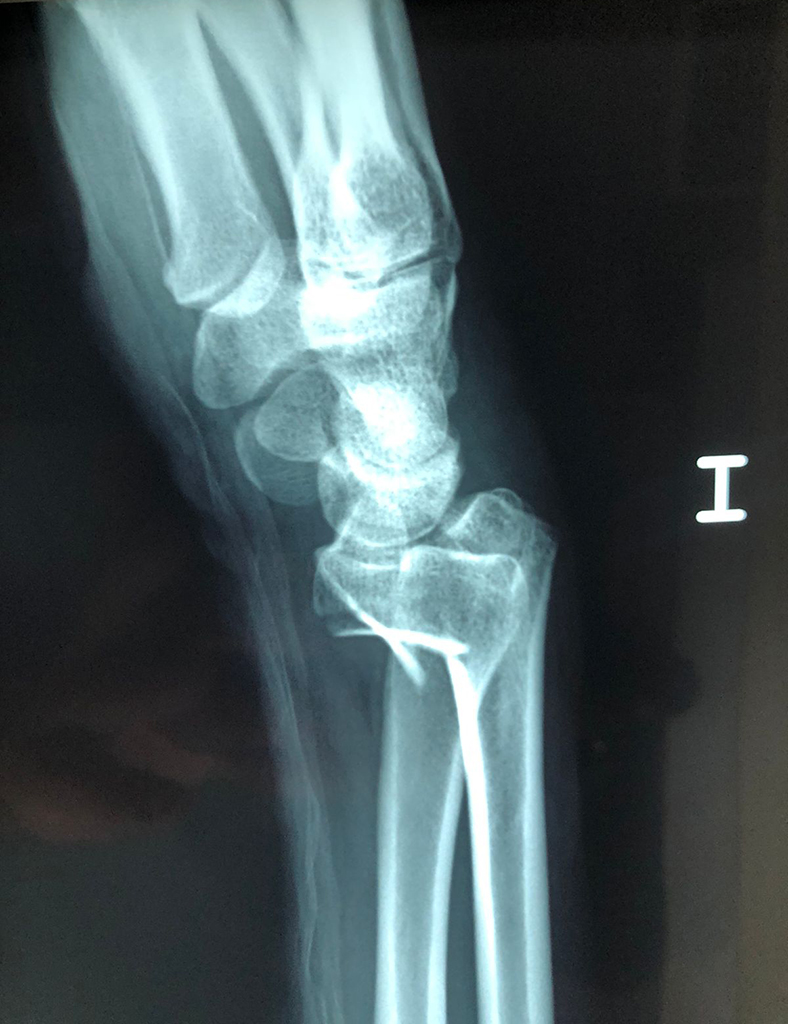

Cirugías de Codo - Cirugías de Muñecas y Manos

Los procedimientos más comunes en cirugía de la mano son aquellos destinados a reparar traumatismos, incluyendo lesiones de tendones, nervios, vasos sanguíneos, y articulaciones; huesos fracturados; y quemaduras, cortes, y otros daños de la piel.